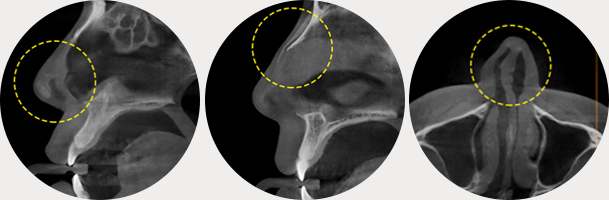

如果將我們的臉比作球,如圖所示,耳下方輪廓不是從正面看最寬的部位,而比最寬部位靠後。

因此除了耳下方輪廓外翻的少數情況,下頜角切除術不會縮小下頜寬度。

WIAD方下巴縮小術透過將皮質整體切除(full thickness corticectomy),實現最卓越的正面改善效果。

如果將我們的臉比作球,如圖所示,耳下方輪廓不是從正面看最寬的部位,而比最寬部位靠後。 因此除了耳下方輪廓外翻的少數情況,下頜角切除術不會縮小下頜寬度。 WIAD方下巴縮小術透過將皮質整體切除(full thickness corticectomy),實現最卓越的正面改善效果。

下頜角切除術

切除下頜角時,切除部位從正面看角度不夠明顯。

皮質切除術

皮質切除術可以明顯縮小從正面看不見部位的線條。